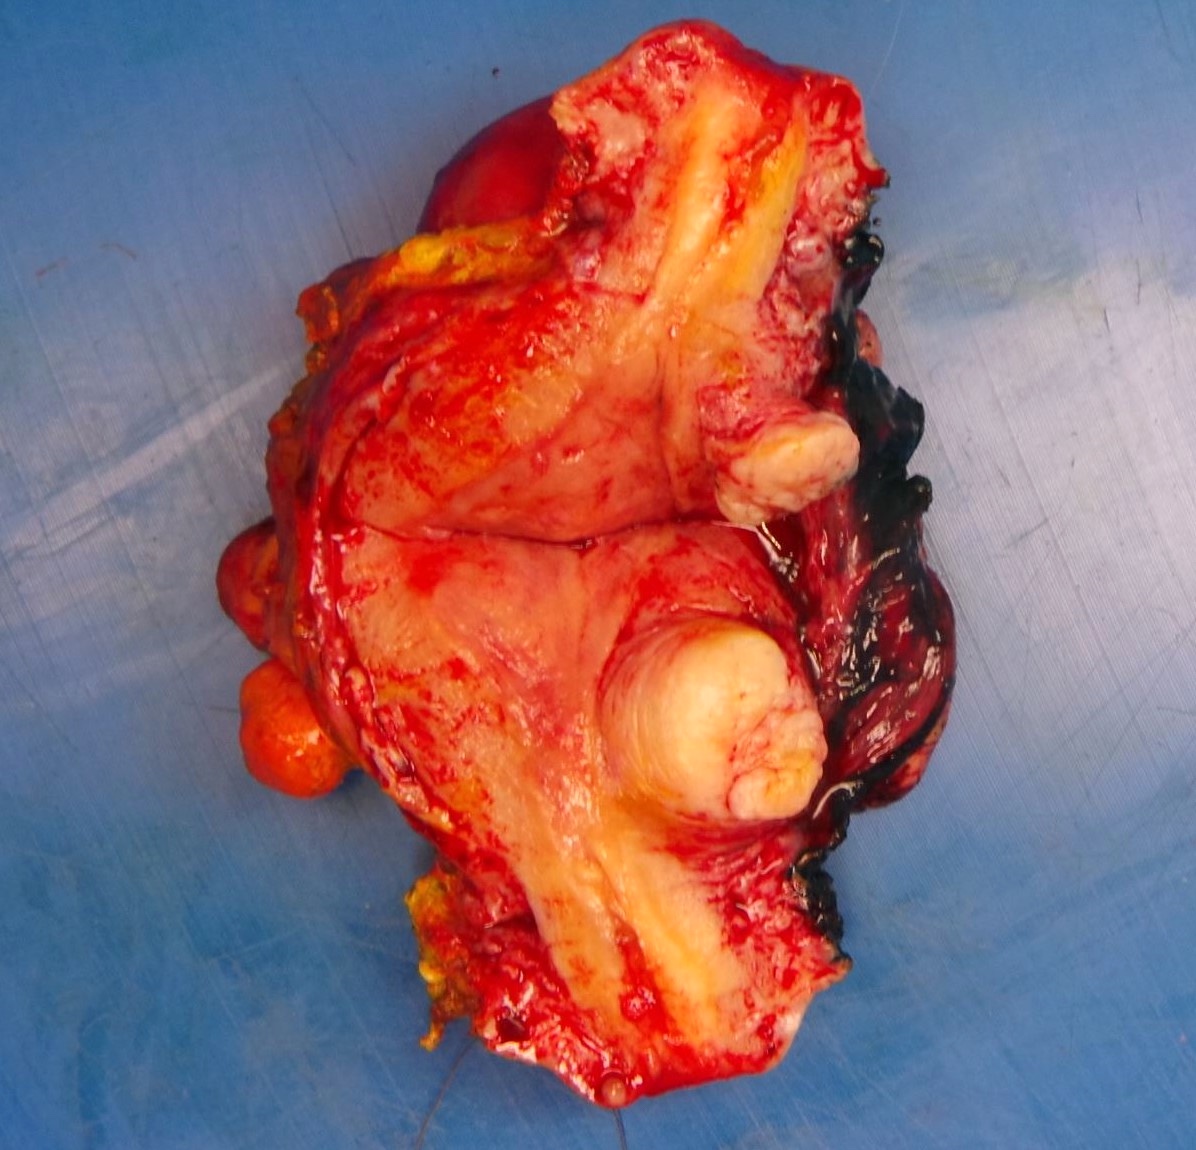

Gross description

- Location in the uterus: intramural, submucosal and subserosal

- Often multiple

- Typically well circumscribed but nonencapsulated

- On cut surface: white or tan-white, whorled, firm, bulging

- Hemorrhage and infarction can be present in large tumors

- Calcifications can be present

- Apoplectic change (foci of hemorrhage) associated with progesterone therapy

Gross images